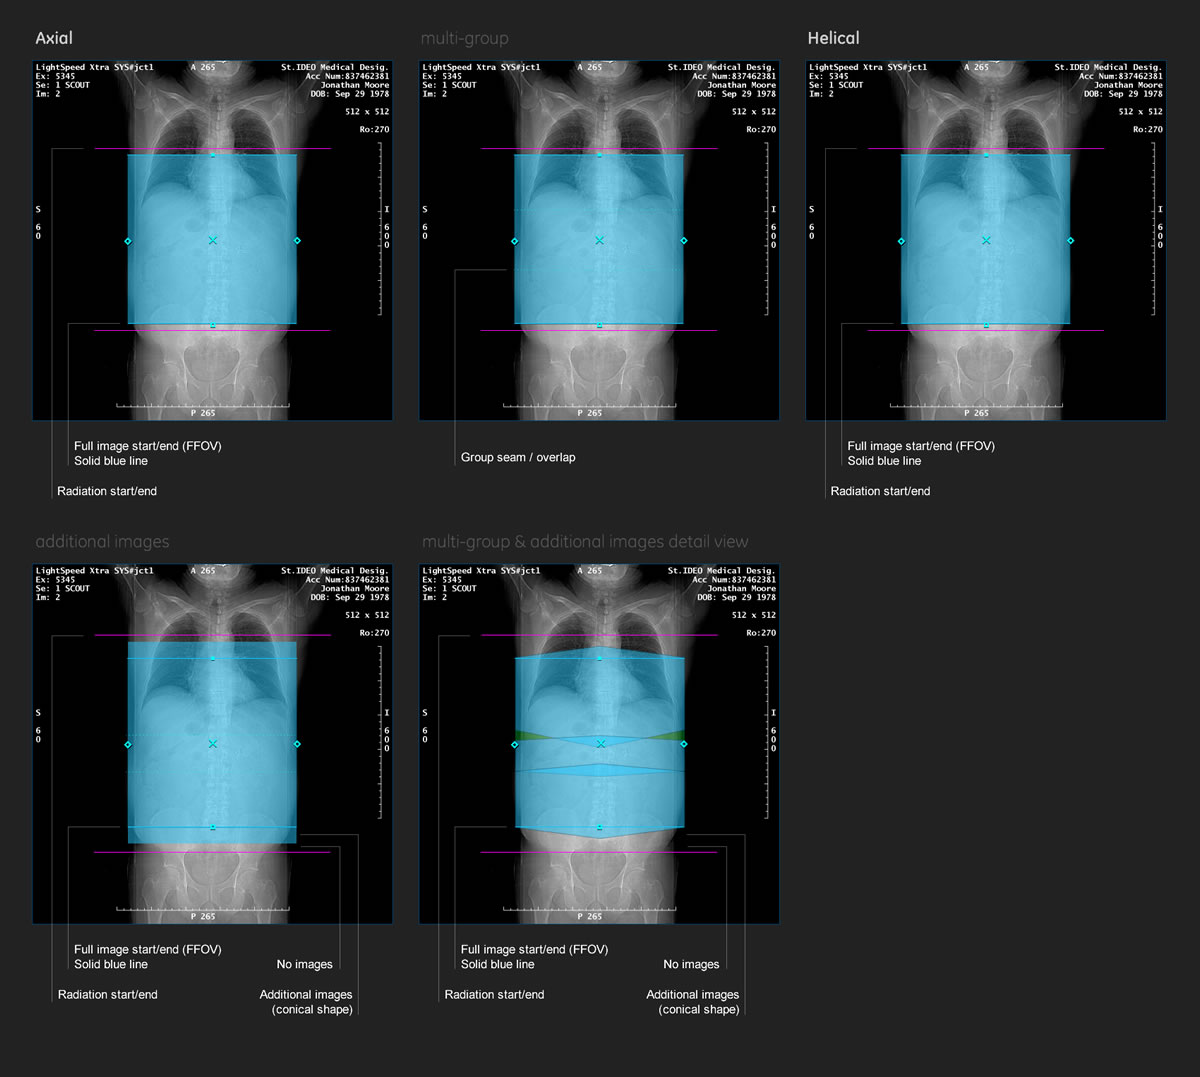

Scan Range / Groups

The unique wide-coverage system presented a unique challenge because of all the new capabilities it provided. New scan range UI had to be developed without complicating the existing systems or confusing the techs.